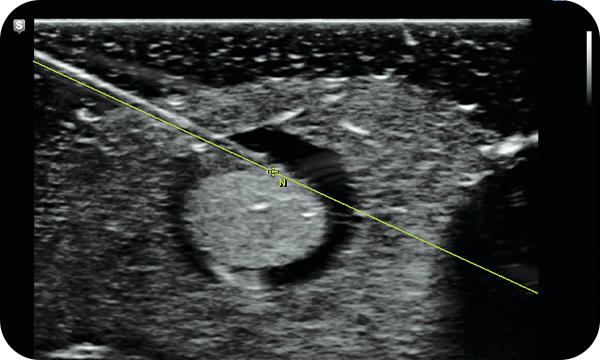

S-Shearwave Imaging™ allows for non-invasive assessment of the stiffness of tissue/lesions liver. The color-coded elastogram, quantitative measurements, dual or single display option, and user-selectable ROI functions are especially useful for the accurate diagnosis liver diseases.

S-Fusion™ for liver enables simultaneous localization of a lesion using real-time ultrasound in conjunction with other volumetric imaging modalities. Samsung's auto registration helps quickly and precisely fuse the images, increasing efficiency and reducing procedure time. S-Fusion™ enables precise targeting during interventional and other advanced clinical procedures.

S-Tracking increases accuracy during interventional procedures by providing a simulated needle path and target mark within the live ultrasound image. Clear Track, one of two functions provided by S-Tracking, ensures accuracy by using a specialized needle with a sensor tip. S-Tracking also includes Virtual Track utilizing conventional needles to provide both accuracy and economic benefit.